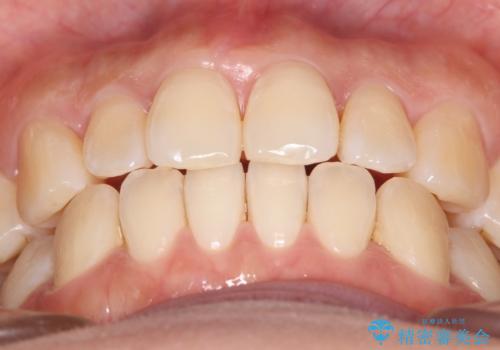

- 上の前歯の捻れを主訴に来院されました。

前歯の捻れとがたつきを改善するために、IPR(歯と歯の間を削る処置)と歯列拡大をすることで歯並びを整えていく治療計画を立てました。

かみ合わせを整えるためにゴム掛けも行いながら、治療していきました。

患者様にマウスピースの使用とゴム掛けを頑張っていただいたおかげでリファイメント(マウスピースの再発注)も1回で終了することができました。